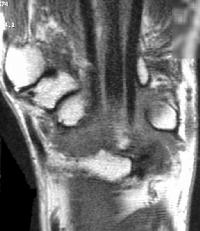

Sections through the carpal tunnel -  looking for a hook of hamate fracture or tendon discontinuity - were read as normal, although there may be a subtle signal irregularity through the hook of the hamate:

Is that a tendon rupture adjacent to the pisotriquetral joint?